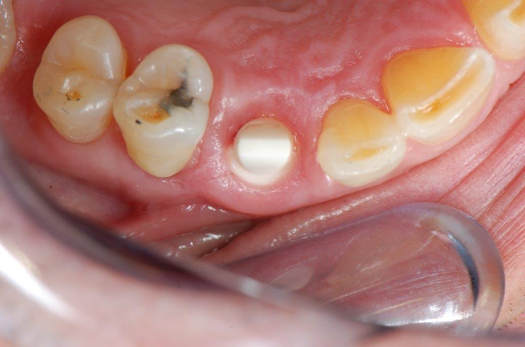

Fig 11. Preoperative healed sites.

Figure 11

Figure 10 through Figure 13 show the preoperative x-ray and the sequence of beginning with healed sites through the surgical placement of the implants. The implants were protected by an Essix-style wound-protection removable retainer for approximately 12 weeks. After the integration phase, the implants and the natural dentition were prepared using traditional crown-and-bridge high-speed diamond and zirconia cutting burs to remove decay and existing restorative materials, to complete and refine the natural-tooth structures to receive full-crown coverage, and to prepare and refine gingival margins of the zirconia implants where needed.